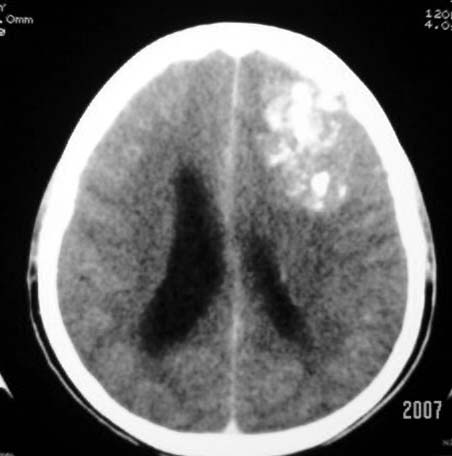

标题: CT7268:左额顶部病变增强片. [打印本页]

标题: CT7268:左额顶部病变增强片.

比较典型的少枝胶质细胞瘤ct表现,局部额骨垂直板有侵蚀变薄。

左额叶病灶内条片状高密度是钙化吗?是的话考虑少支胶质瘤可能大。不然有脑血畸形伴出血可能。

左侧额顶叶有条带状钙化的不规则形占位,增强呈不均匀轻度强化,局部颅骨受侵蚀变薄,典型的少支胶质细胞瘤。

比较典型的少枝胶质细胞瘤ct表现,局部额骨垂直板有侵蚀变薄